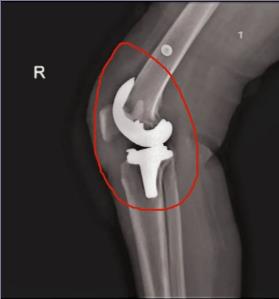

近日淄博市第四人民医院骨二组成功为一例类风湿性关节炎患者成功实施关节置换术。患者因类风湿性关节炎,多年来膝关节不能伸直,关节反复肿胀,行走受限,疼痛无时无刻不在折磨着他,不仅无法工作并且严重影响生活质量。患者入院后,骨科手术团队仔细为患者行体格检查,制定详细的手术方案,术后在骨二组医护人员的精心治疗和护理下,术后五周,患者的双膝基本活动自如。

膝关节置换手术对晚期大关节畸形和功能障碍的患者行关节置换手术治疗是最终有效恢复正常生活及提高生活质量的有效治疗手段。